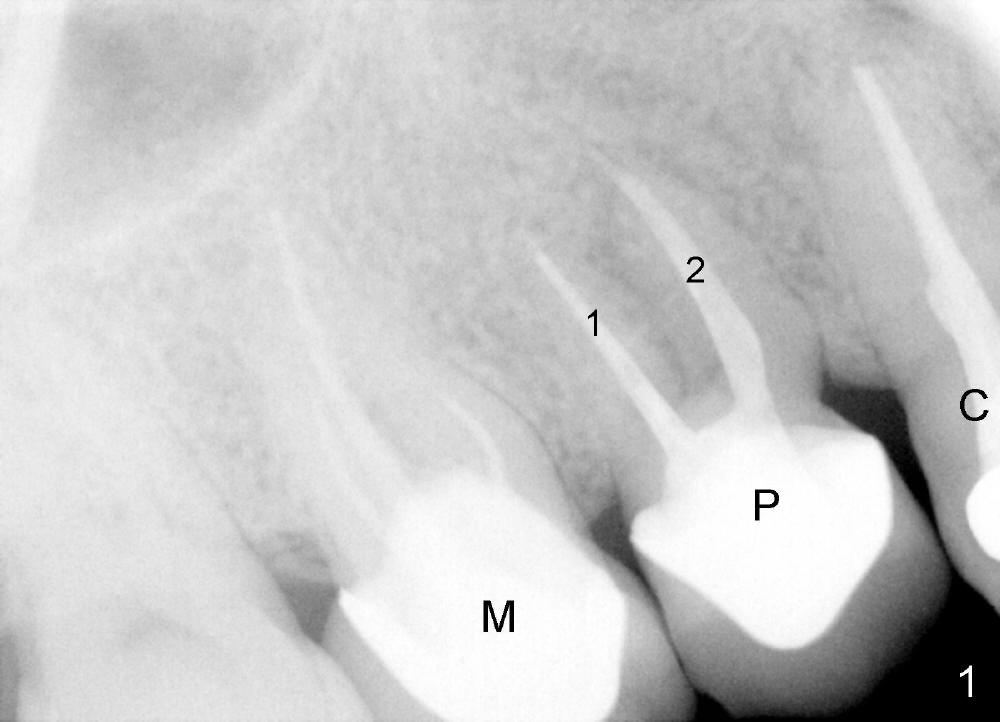

A 45-year-old man has multiple restorations. There is persistent pain in the upper right premolar (Fig.1 P, between canine (C) and the 1st molar (M)). This preop PA is taken several years before symptoms develop. It shows that this premolar is malpositioned: two roots (1,2) are aligned mesiodistally. The distal periodontal pockets are deep, consistent with root fracture.